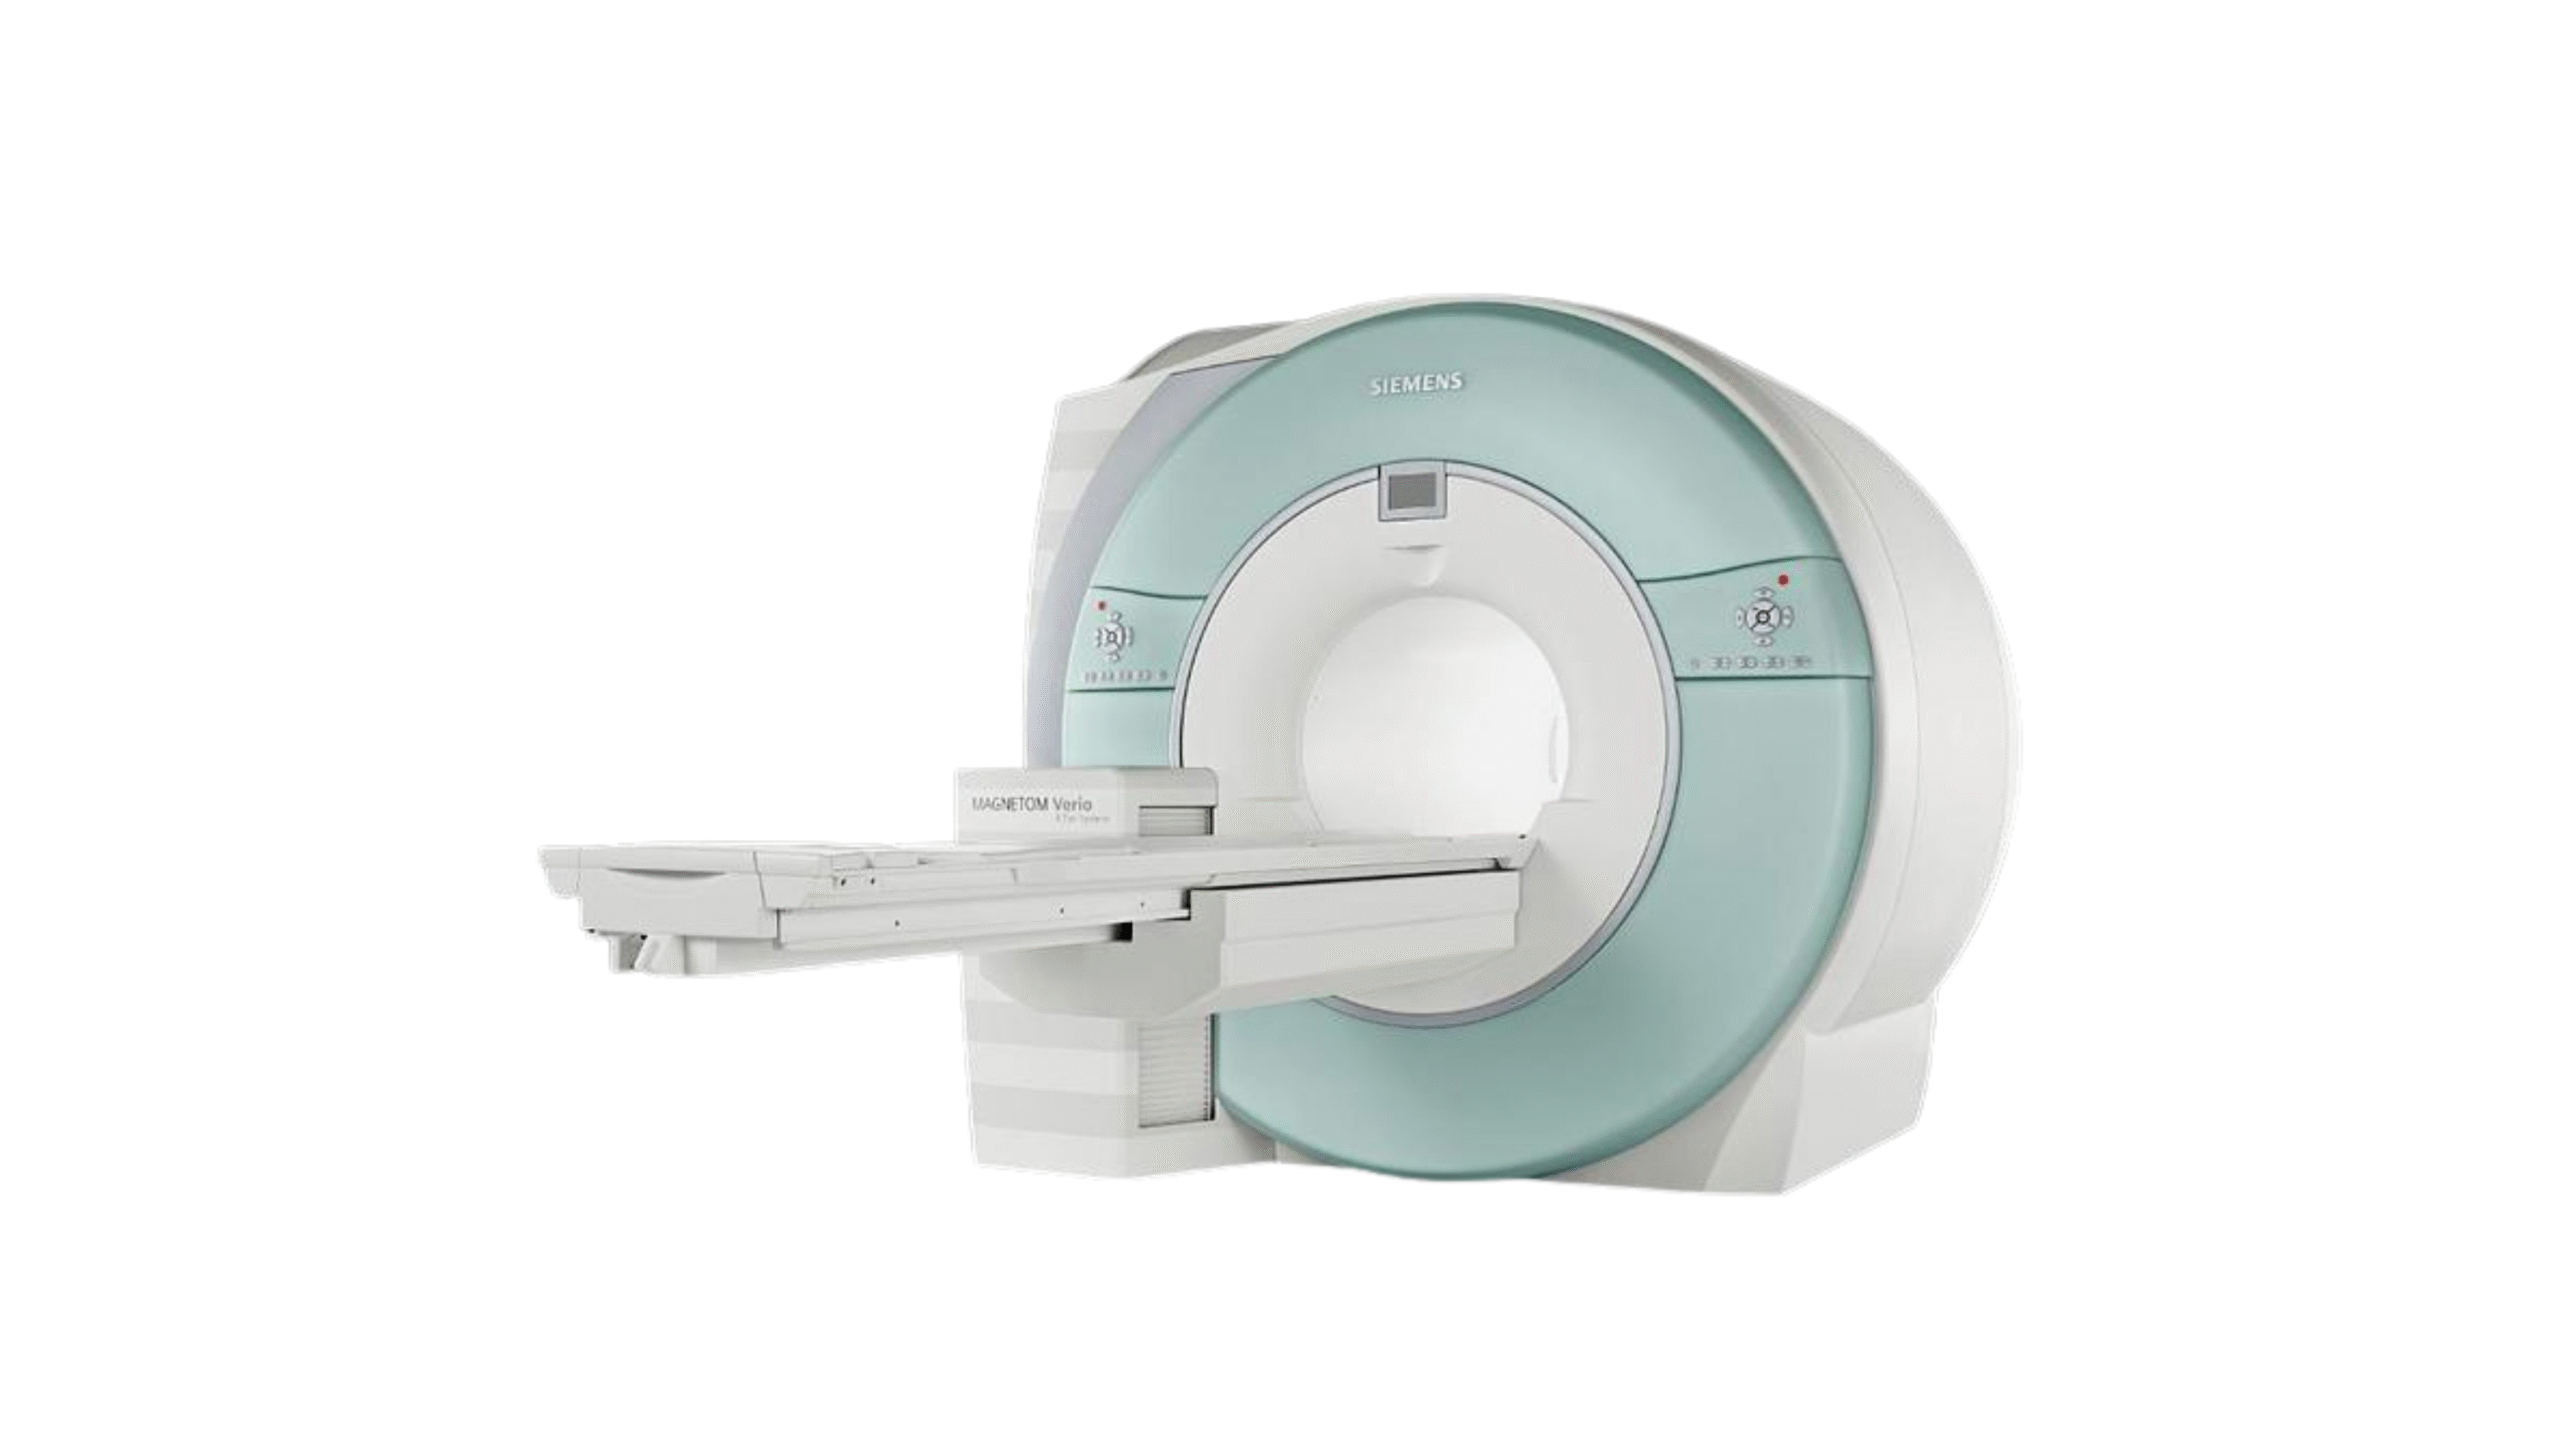

Medical equipment marketplace

Products

Medem ltd. is a global medical distributor of equipment and consumables.

We provide reliable service for our partners all around the globe. Offering well-known brands such as Fujifilm Healthcare, Carestream Health, Konica Minolta Healthcare and many others. Minimum order quantity is 1 pallet.